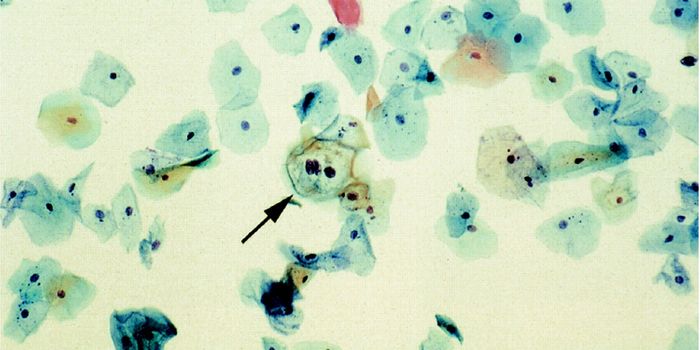

FEB 16, 2016Clinical & Molecular DXThe American College of Obstetricians and Gynecologists (ACOG) recently revised and updated its recommendations for cerv ...